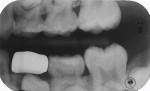

A 7-year-old girl presented with a fractured disto-occlusal, resin-modified glass-ionomer restoration on her primary mandibular left first molar that had been placed 30 months prior. The damage had permitted new caries to infect the distal third of the tooth (Figure 13). After local anesthesia was achieved and a rubber dam was placed, the carious tooth structure was debrided with a large round bur at slow speed, and the exposed dentin was covered with the resin-modified calcium silicate liner (Figure 14). Occlusal reduction was achieved in the same manner as in the previous case (Figure 15), and the axial reduction was cut to a shoulder preparation with the idea that the zirconia crown edge would seat onto the prepared margin (Figure 16). Two vertical grooves were included on the buccal aspect of the preparation to add to the surface area to improve luting cement adhesion. After the pink try-in crown established the proper size, the selected zirconia crown was filled with the luting cement and seated with finger pressure (Figure 17). The zirconia crown was observed 26 months after cementation (Figure 18 and Figure 19). At 33 months, the presence of advanced distal root resorption and eruption of the underlying premolar necessitated extraction of the crowned tooth (Figure 20 and Figure 21).